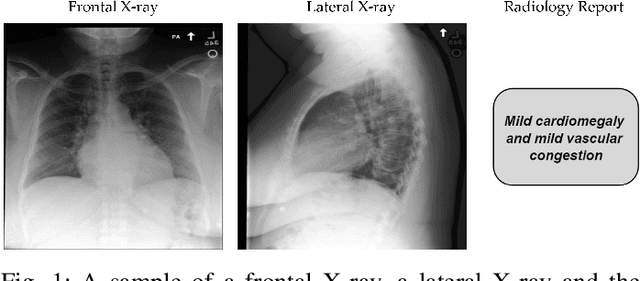

Abstract:Generative models have revolutionized Artificial Intelligence (AI), particularly in multimodal applications. However, adapting these models to the medical domain poses unique challenges due to the complexity of medical data and the stringent need for clinical accuracy. In this work, we introduce a framework specifically designed for multimodal medical data generation. By enabling the generation of multi-view chest X-rays and their associated clinical report, it bridges the gap between general-purpose vision-language models and the specialized requirements of healthcare. Leveraging the MIMIC-CXR dataset, the proposed framework shows superior performance in generating high-fidelity images and semantically coherent reports. Our quantitative evaluation reveals significant results in terms of FID and BLEU scores, showcasing the quality of the generated data. Notably, our framework achieves comparable or even superior performance compared to real data on downstream disease classification tasks, underlining its potential as a tool for medical research and diagnostics. This study highlights the importance of domain-specific adaptations in enhancing the relevance and utility of generative models for clinical applications, paving the way for future advancements in synthetic multimodal medical data generation.

Abstract:Artificial Intelligence is revolutionizing medical practice, enhancing diagnostic accuracy and healthcare delivery. However, its adaptation in medical settings still faces significant challenges, related to data availability and privacy constraints. Synthetic data has emerged as a promising solution to mitigate these issues, addressing data scarcity while preserving privacy. Recently, Latent Diffusion Models have emerged as a powerful tool for generating high-quality synthetic data. Meanwhile, the integration of different modalities has gained interest, emphasizing the need of models capable of handle multimodal medical data.Existing approaches struggle to integrate complementary information and lack the ability to generate modalities simultaneously. To address this challenge, we present MedCoDi-M, a 6.77-billion-parameter model, designed for multimodal medical data generation, that, following Foundation Model paradigm, exploits contrastive learning and large quantity of data to build a shared latent space which capture the relationships between different data modalities. Further, we introduce the Multi-Prompt training technique, which significantly boosts MedCoDi-M's generation under different settings. We extensively validate MedCoDi-M: first we benchmark it against five competitors on the MIMIC-CXR dataset, a state-of-the-art dataset for Chest X-ray and radiological report generation. Secondly, we perform a Visual Turing Test with expert radiologists to assess the realism and clinical relevance of the generated data, ensuring alignment with real-world scenarios. Finally, we assess the utility of MedCoDi-M in addressing key challenges in the medical field, such as anonymization, data scarcity and imbalance learning. The results are promising, demonstrating the applicability of MedCoDi-M in medical contexts. Project page is at https://cosbidev.github.io/MedCoDi-M/.